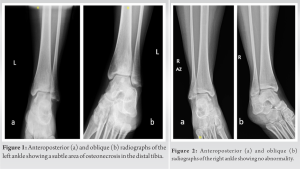

A 38-year-old non-smoker, non-alcoholic previously healthy woman presented with a complaint of bilateral ankle pain, with the left ankle being more affected, which had been present for the past 5 years. Medical history is positive only for 10 years of hypothyroidism treated with Euthyrox. Her pain started intermittently and gradually became constant, radiating to both feet and knees and was exacerbated by ambulation, with partial relief with non-steroidal anti-inflammatory drugs (NSAIDs). The patient also reported severe night pains. Physical examination revealed tenderness over the left distal tibia with a painful range of motion of both ankles, more so on the left. No swelling, redness, or edema were observed. Bilateral ankle radiographs were obtained, which showed a small radiolucent circumferential area suggestive of ON of the left distal tibia (Fig. 1).

Radiographs of the right distal tibia were unremarkable (Fig. 2).